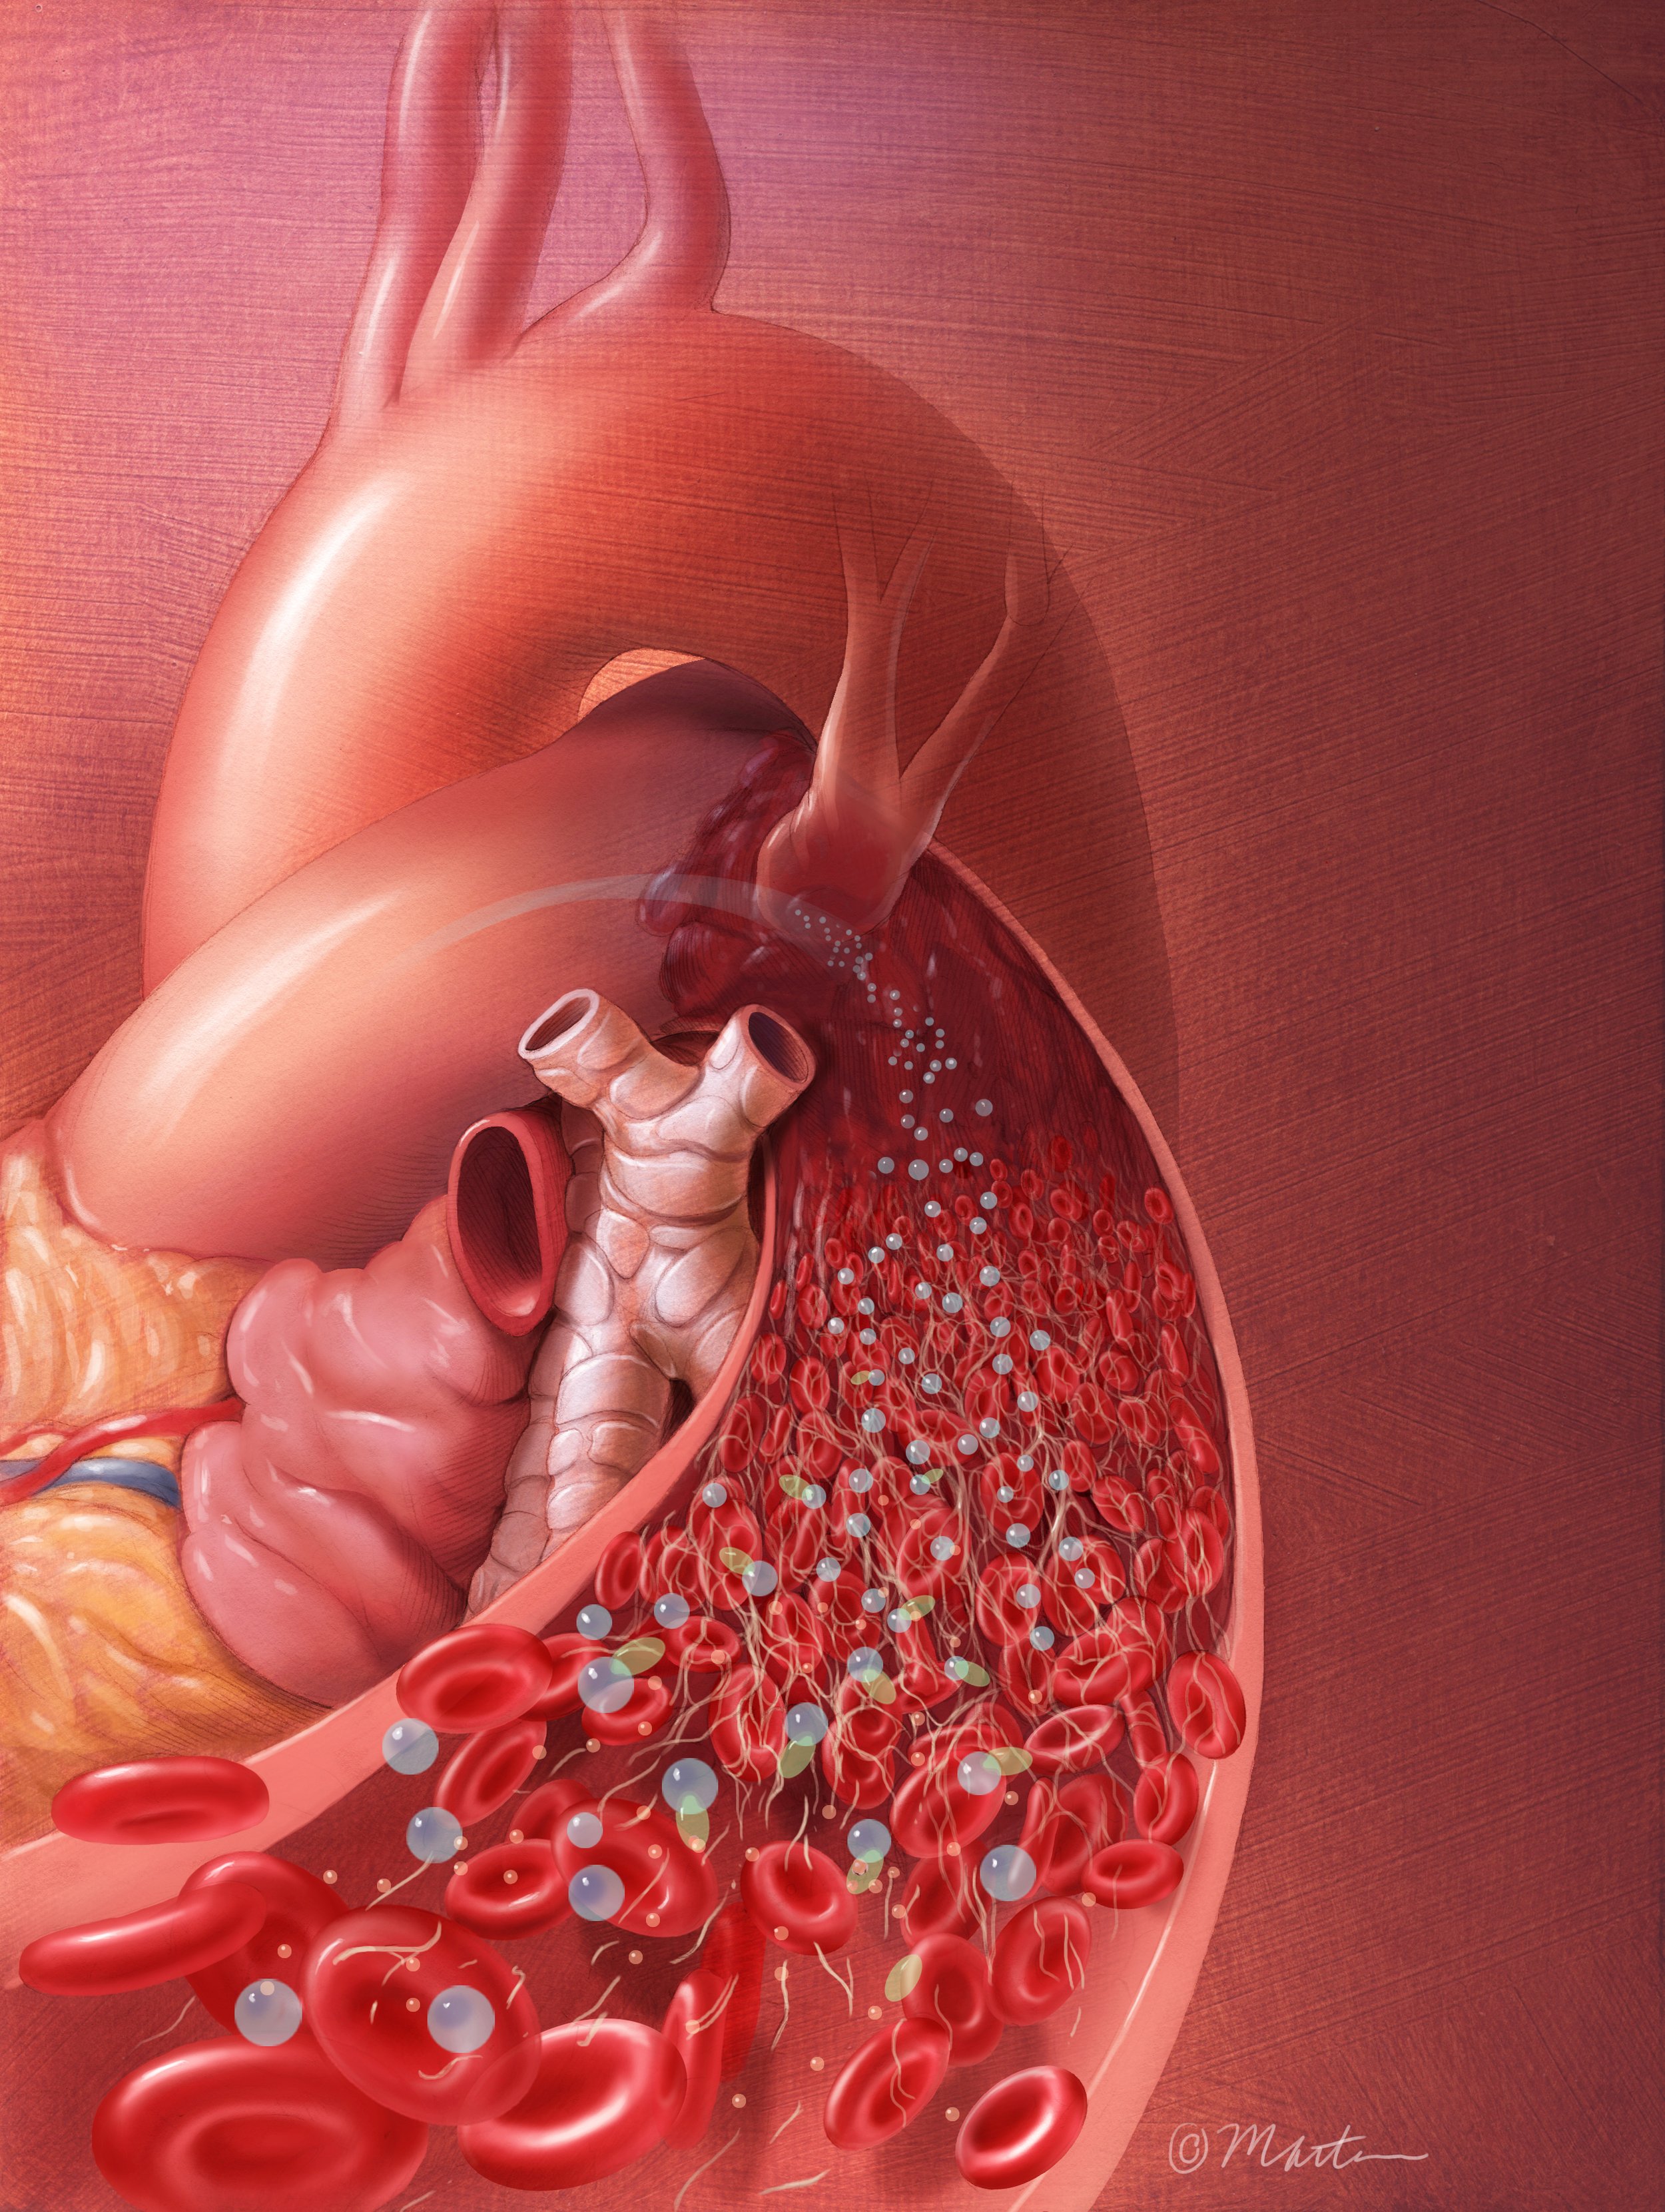

ECMO